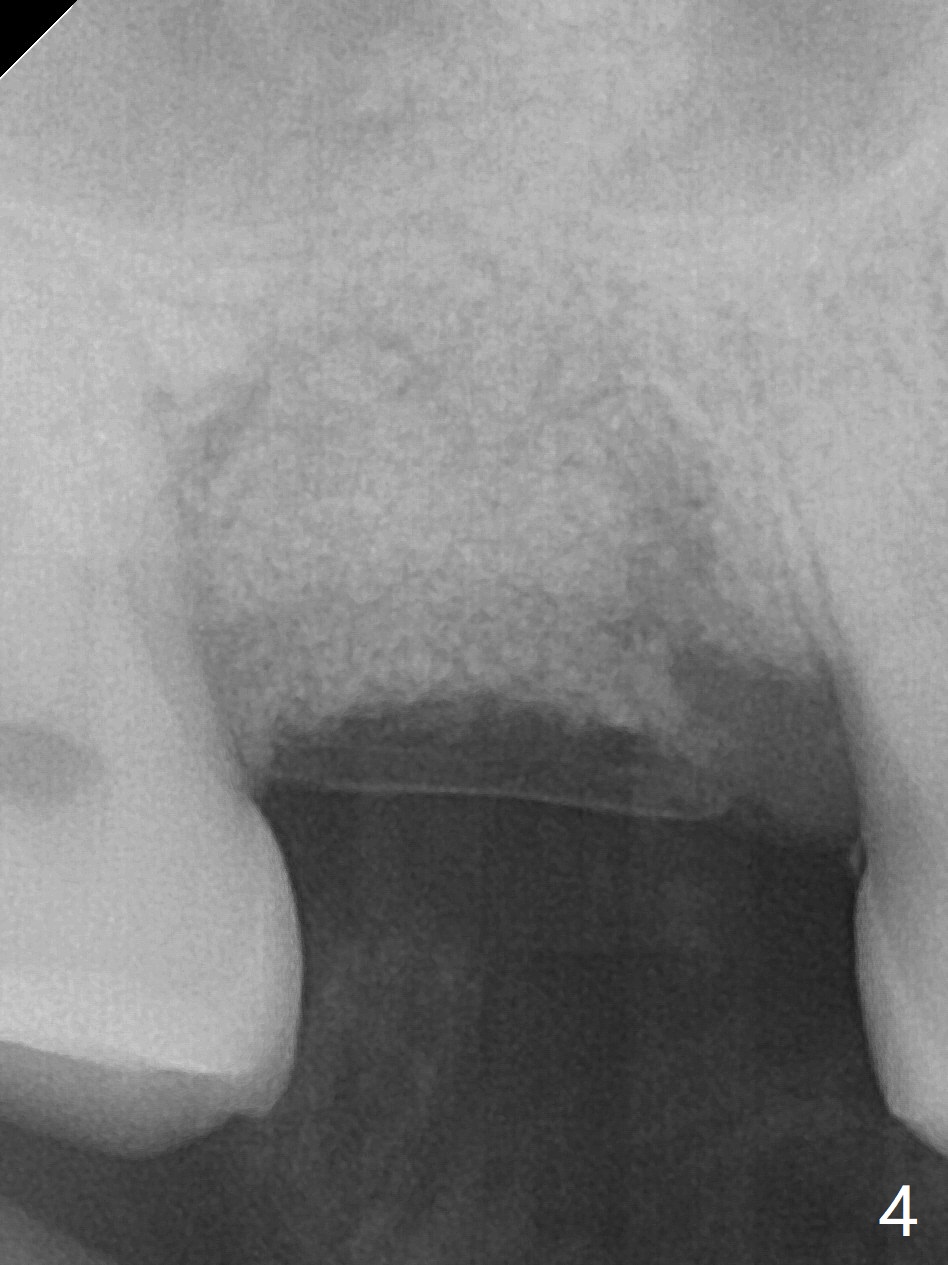

Not long postop, the patient called saying that #2 provisional had dislodged. Due to his busy schedule and coronavirus outbreak, he returns nearly 4 months postop. The abutment is distalized and loose with the underlying implant (5x9 mm). The latter is removed before local anesthesia (Fig.1 distal defect). After initial debridement, a 2.2x13 mm drill is used with a guide of 12 mm offset, followed by insertion of a 4.5x11 mm dummy implant with barely stability (Fig.2). A 5.5x9 mm is placed free hand initially, followed by guide with stability. But the implant has uncovered threads distolingual. Thorough debridement reveals that the sinus membrane has a small perforation. After placement of a piece of Osteogen plug, cortical chip and Vanilla hydrated with .25 cc of GEM21S is packed into the site with a condenser (Fig.3,4). The graft is fixed in place with Perio glue, followed by a piece of GEM Cap with the glue. Three to 4 months later, take CT for healing confirmation. Try to place a shorter implant (e.g., 5x7 mm) without getting into the sinus to reduce infection. In fact the Cap does not stay in place with loss of bone graft (8 days postop).